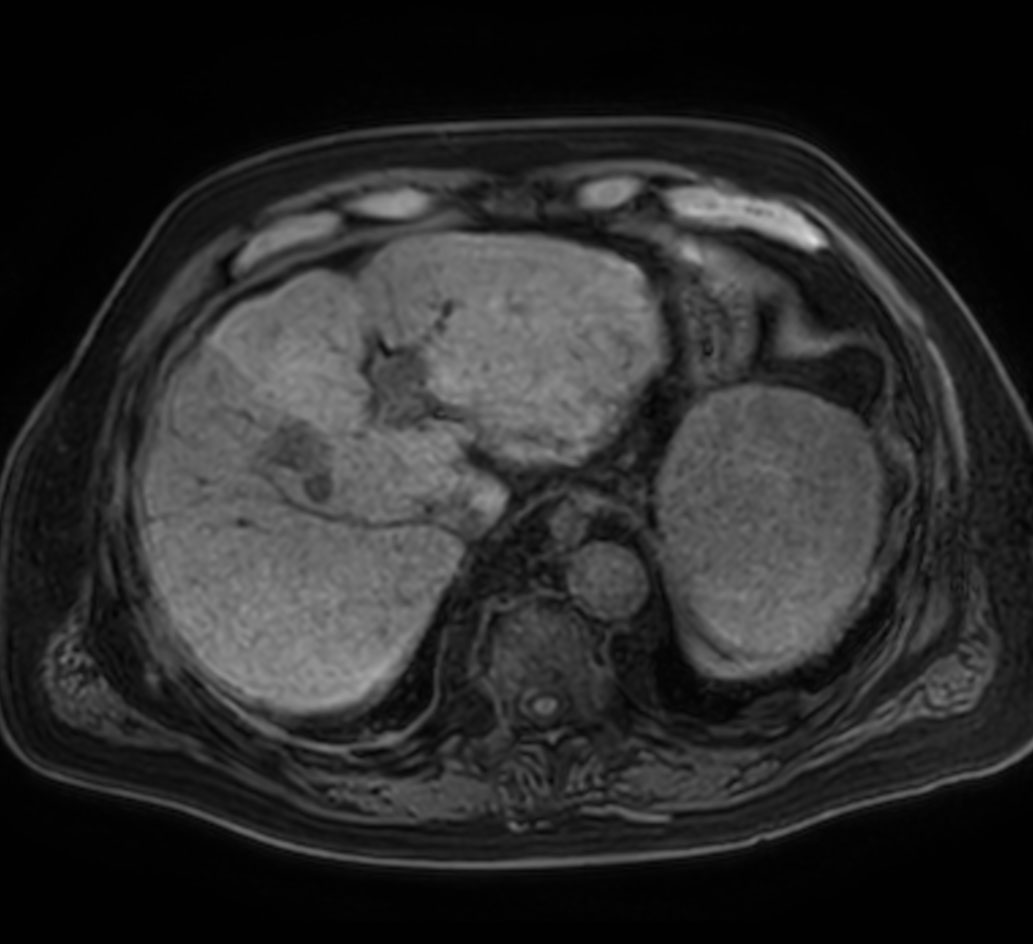

Axial T1w mDIXON XD (Water only)

Axial T1w mDIXON XD (In Phase)

Axial T1w mDIXON XD (Out Phase)